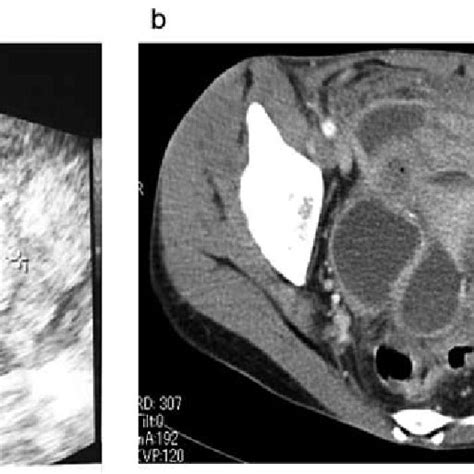

- Circ_0001273 Was Overexpressed In Ec Tumor Tissues And Cell Lines. (a ...